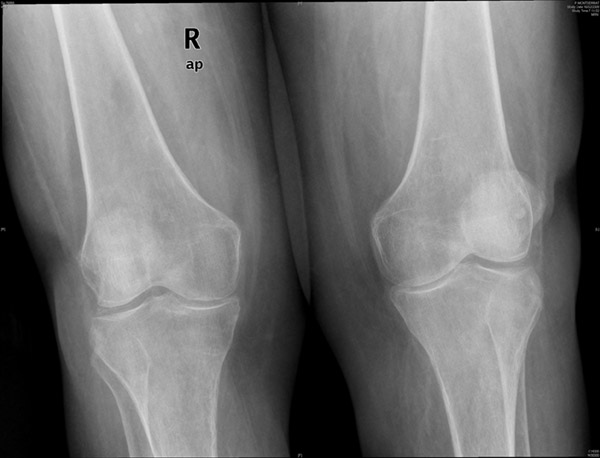

APR Gonartrosis

Prótesis completa bilateral de rodillas.